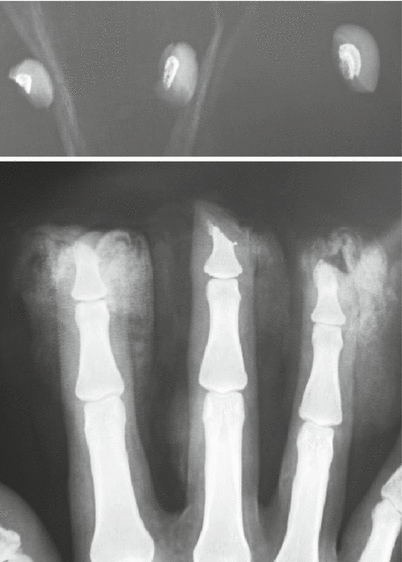

Fig. 8.19

(a, b) Procedure 9: Appearance immediately after surgery

Note

It took 92 min to reattach the three fingers.

Liberal amounts of ointment are continually applied to the transplanted nail bed to prevent it from drying out, and the scab is not removed for 2 weeks.

Fig. 8.20

(a, b) Procedure 10: Appearance of nails 1 year later. Healthy nail growth can be seen. The bulge on the palmar side of the fingertip has been accurately recreated. Return of sensory function is also recognized

Fig. 8.21

Procedure 11: X-ray image 1 year after surgery. No bone absorption in the finger tip. (Some photos reproduced from Hirase, Y., et al.: A new reattachment procedure for fingers amputated at the nail bed level. Journal of Japanese Society for Surgery of the Hand 20:501–504, 2003)